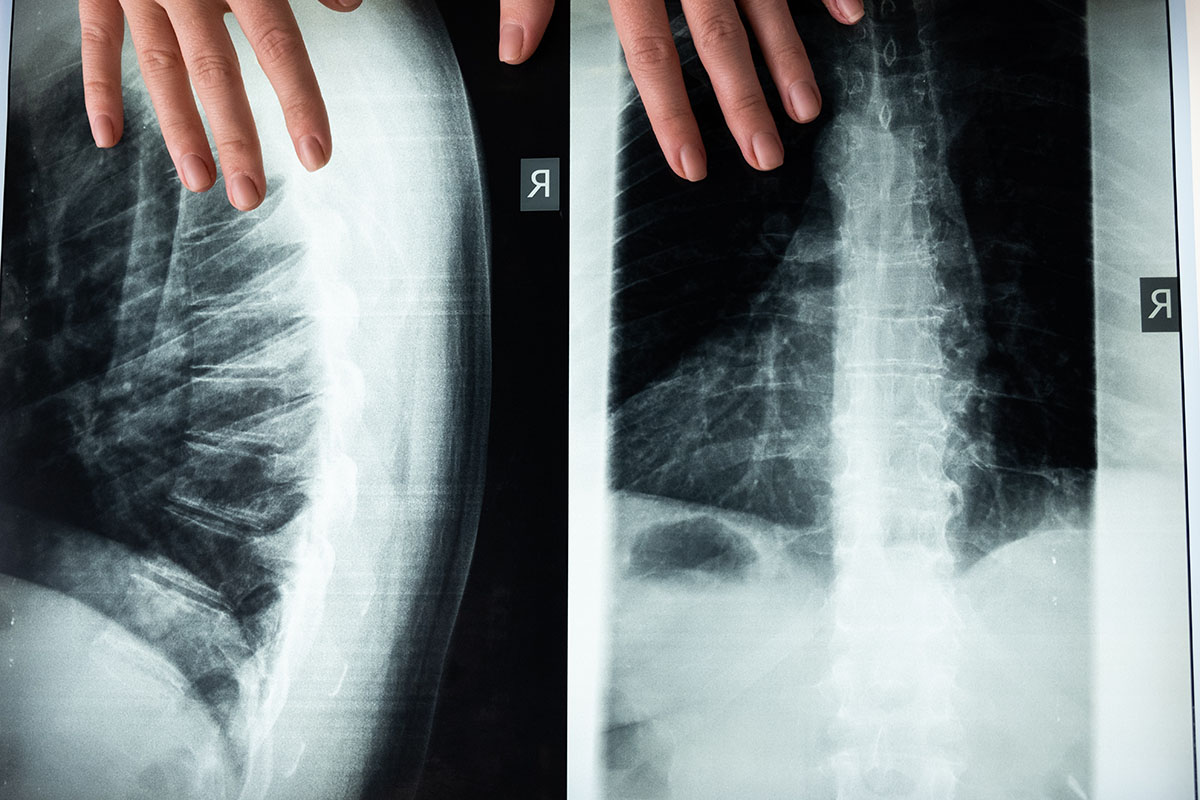

Η μέτρηση της οστικής πυκνότητας θα πρέπει να γίνεται τακτικά, ήδη από την έκτη δεκαετία της ζωής μας. Οι γυναίκες άνω των 65 και οι άνδρες άνω των 70 ετών (συχνά και σε νεότερες ηλικίες εάν υπάρχει σαφής ένδειξη ή βεβαρυμμένο οικογενειακό ιστορικό) θα πρέπει να πραγματοποιούν τακτικούς ελέγχους για μέτρηση της οστικής πυκνότητας. Ασθενείς με παθήσεις της σπονδυλικής στήλης, όπως κύφωση και σκολίωση, μπορεί να χρειαστούν έλεγχο σε πιο τακτική βάση ώστε να περιοριστούν οι επίπονες συνέπειες της οστεοπόρωσης στα ήδη επιβαρυμένα οστά τους. Τα κατάγματα της σπονδυλικής στήλης σήμερα, δείχνουν υψηλό ποσοστό θνησιμότητάς, αντίστοιχο με τα κατάγματα ισχίου.